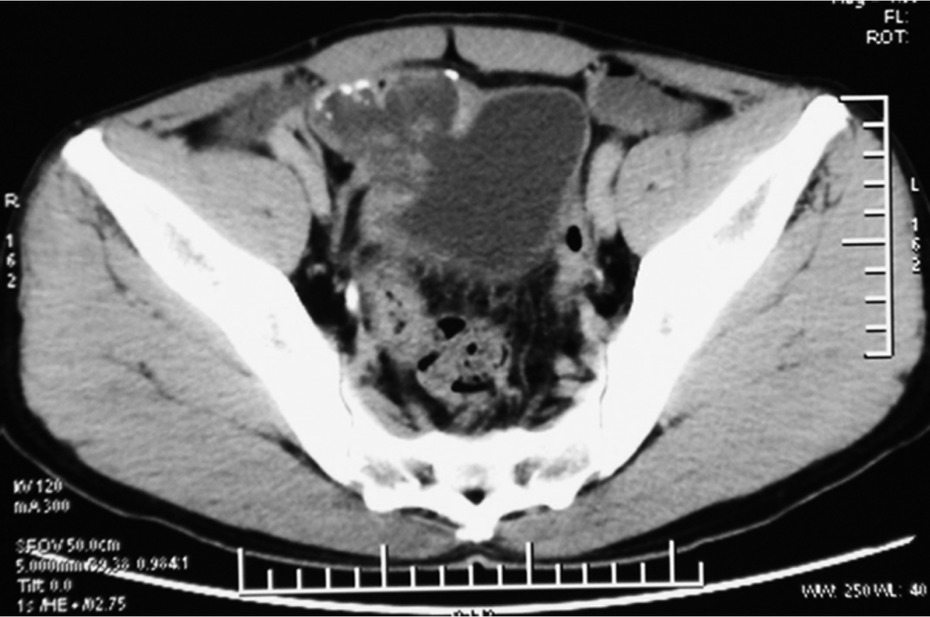

A 54-years old man with a 6-month history of intermittent episodes of irritative voiding symptoms of the bladder and weight loss was admitted. The patient did not have any gastrointestinal symptoms such as pain, obstruction or melena, and he presented a negative medical history for gastrointestinal diseases. The physical examination was negative. An urine analysis revealed 30 white blood cells and 12 red blood cells per high power field. No malignant cells were observed in the urine. The carcinoembryonic antigen level was normal. The enhanced pelvic computed tomography (CT) scan revealed an irregular and slightly higher density (Figure 1), with the largest cross-section of 5.2 cm×4.8 cm. Its CT value was slightly higher than the intravesical CT value. There was some punctate calcification on the edge and inside the hyperdense area. A cystoscopy showed an edematous broad opening with mucinous components in the right posterior wall of the bladder (Figure 2).

CT scan shows an irregular slightly higher density. The largest cross-section diameter was 5.2 cm×4.8 cm and its CT value was slightly higher than the intravesical CT value. There was some punctate calcification on the edge and inside the hyperdense area.